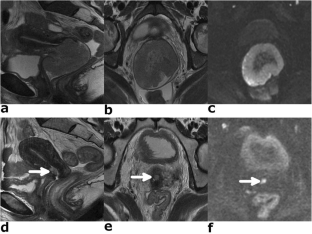

Fig. 1

Fig. 2

Fig. 3

Fig. 4

Fig. 5

Fig. 6